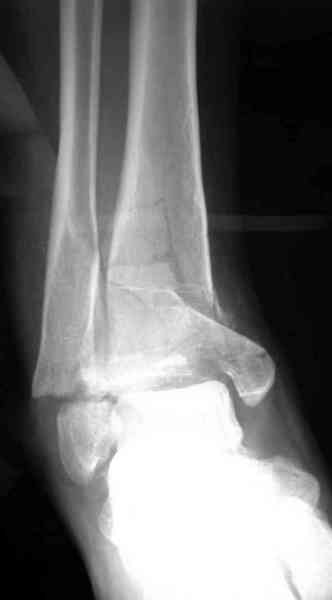

Яков изложил все необходимые аспекты лечения переломов пилона, и, не желая менять тему, решил выставить нашу точку зрения в двух клинических примерах.

При лечении внутрисуставных переломов типа "Pilon"

или "Tibial Plateau" на голени, применение простых

наружных фиксаторов типа "Spanning ExFix" или "Travelling ExFix" стал одним из стандартом этапного лечения.

Первичная пластина или интрамедуллярный фиксатор на малоберцовую зависит от характера перелома, косые и многооскольчатые пластинами, а поперечных можно интрамедуллярными фиксаторами. Восстановленная длина малоберцовой служит ориентиром и помогает определению высоты большеберцовой во время восстановления.

Переломы пилона сопровождаются ударом со сминанием в метафизарной части большеберцовой, то есть со значительной потерей костного объема.

При репозиции суставных поверхностей образуются полости в метафизарных отделах, без заполнения их

структуральными элементами невозможно предохраниться от посттравматической деформации. Латеральная колонна удерживается малоберцовой поэтому голень деформируется в варус.

Здесь выставлена пара случаев перелома пилона, оба

случая леченные этапным наружным фиксатором.

Второй случай фиксирован аппаратом Илизарова.